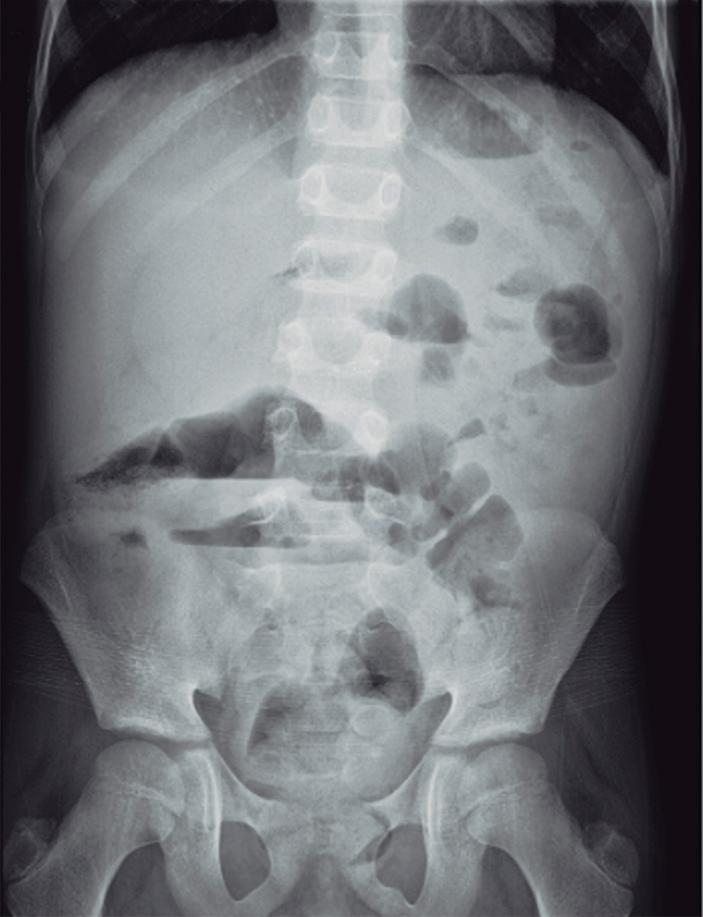

Más allá de lo frecuente. Un desafío diagnóstico en dolor abdominal

Tatiana Noemí Uehara, Juan Manuel de Arechavala, Fernanda Dorado, Verónica Eugenia Corvalán, Fernando Bocelo, Betiana Pucci

Iara Amira Yalis, Marcelo Milocco, Luis María Mercado, Pablo Alberto Farinelli